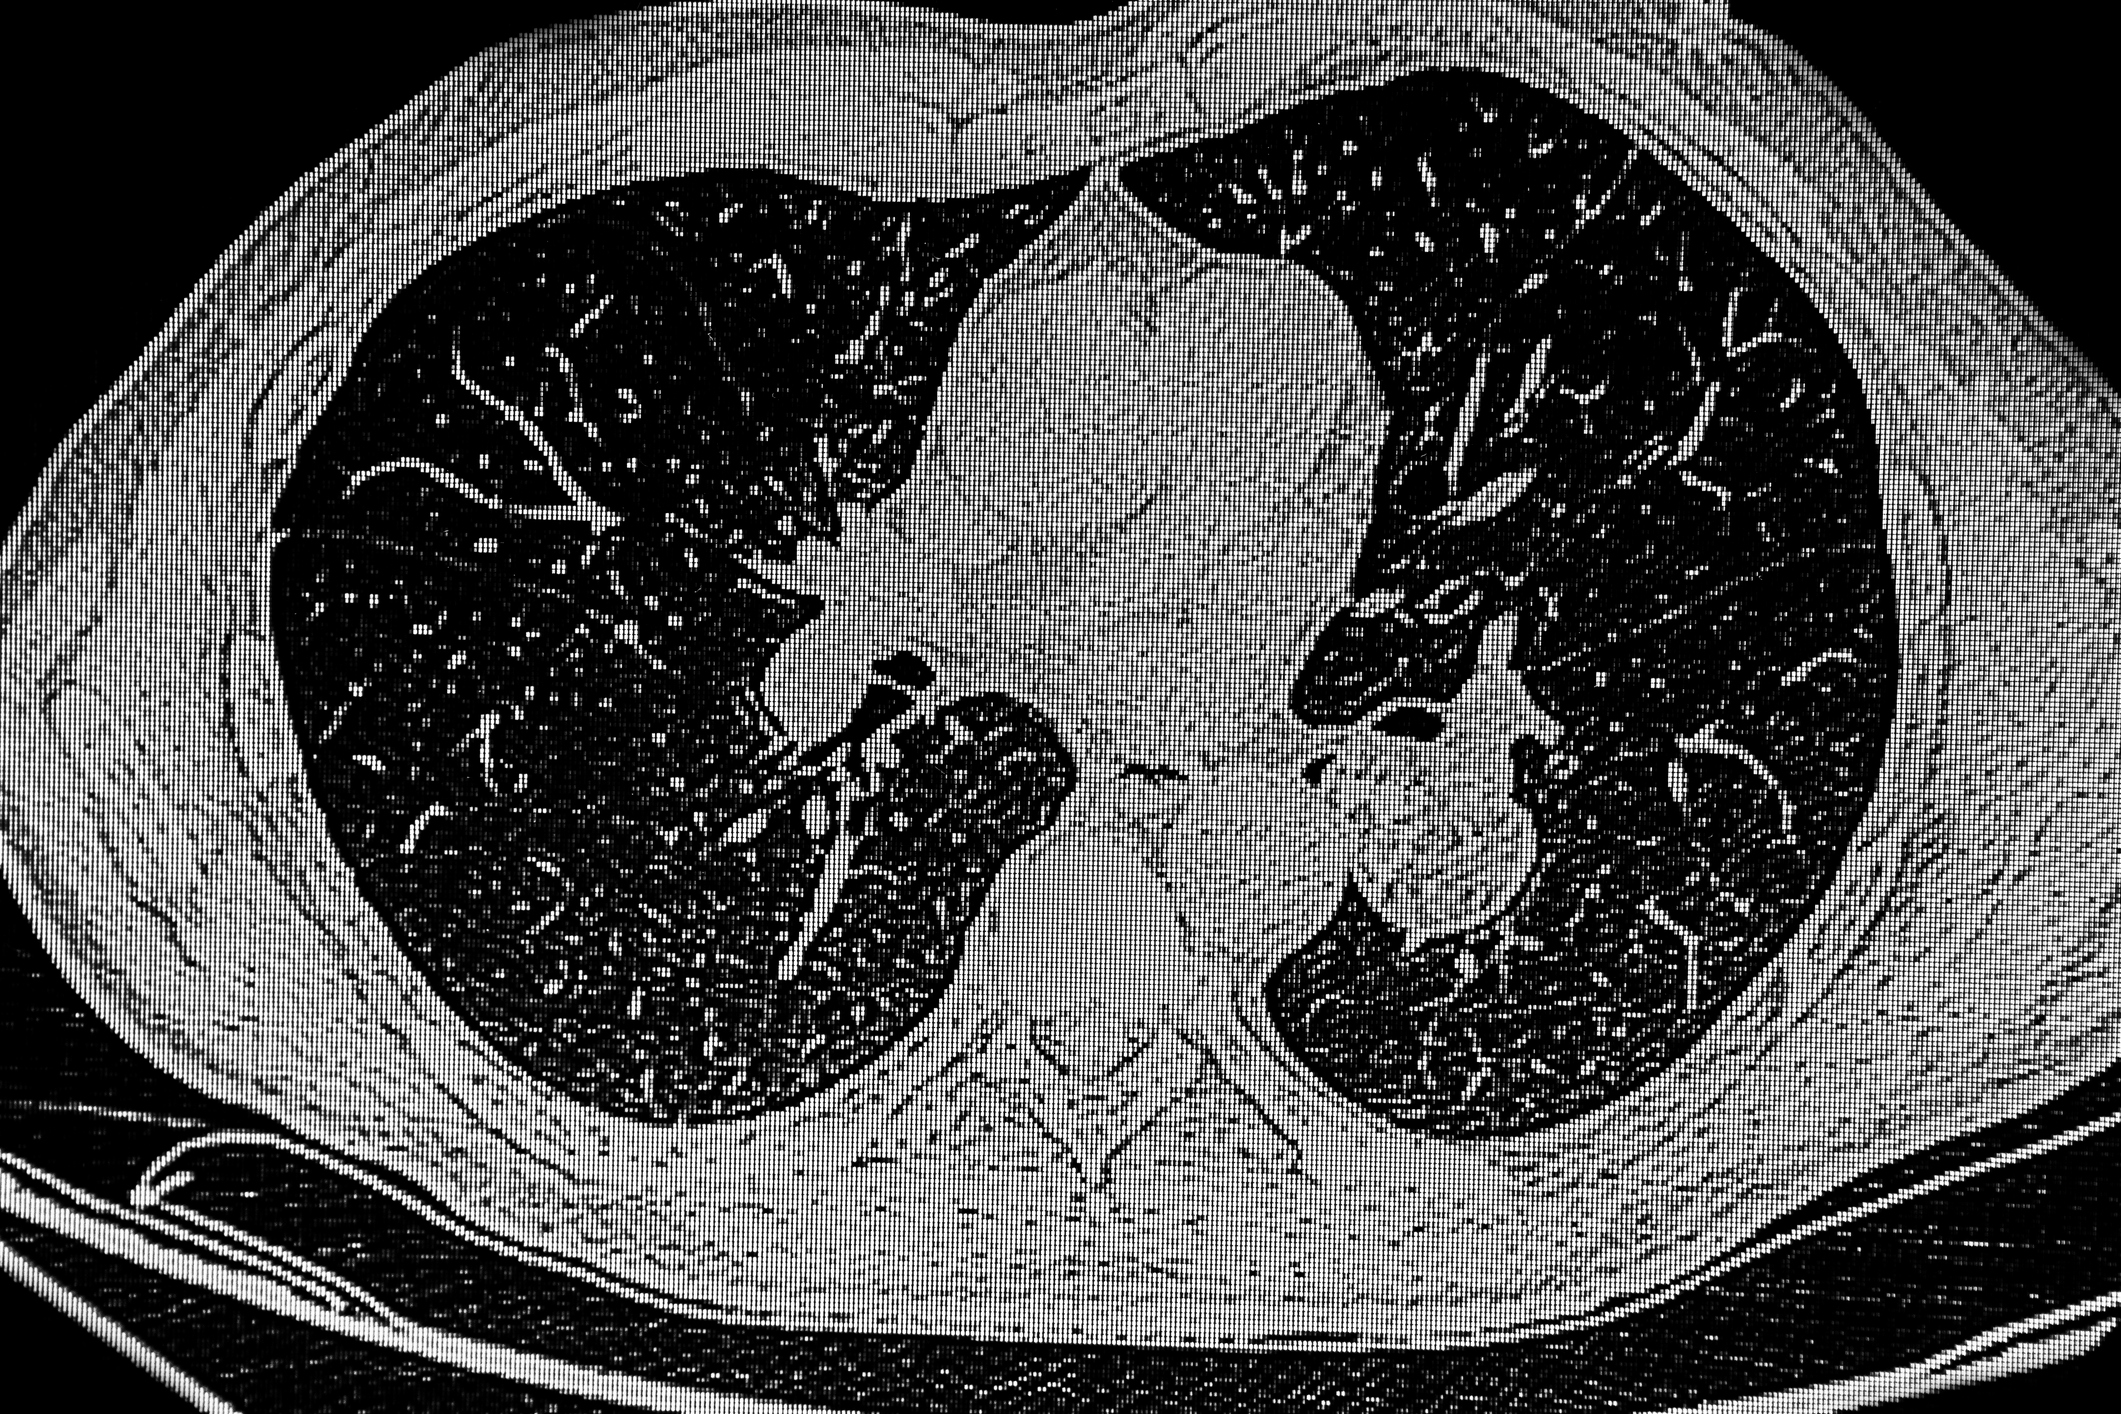

Die Diagnostik respiratorischer Virusinfektionen ist in den letzten Jahren erheblich in das Blickfeld der Medizin gerückt. Während SARS-CoV-2 in den vergangenen Jahren im Mittelpunkt stand, rücken nun zunehmend auch weitere respiratorische Viren wie Influenza und das Respiratorische Synzytial-Virus (RSV) in den Fokus der Fachwelt. Im klinischen Alltag besteht für das medizinische Personal die Herausforderung vor allem darin, die richtigen diagnostischen Methoden für die jeweilige klinische Situation auszuwählen, um eine präzise und zeitnahe Diagnose zu ermöglichen und darauf aufbauend Massnahmen einzuleiten.